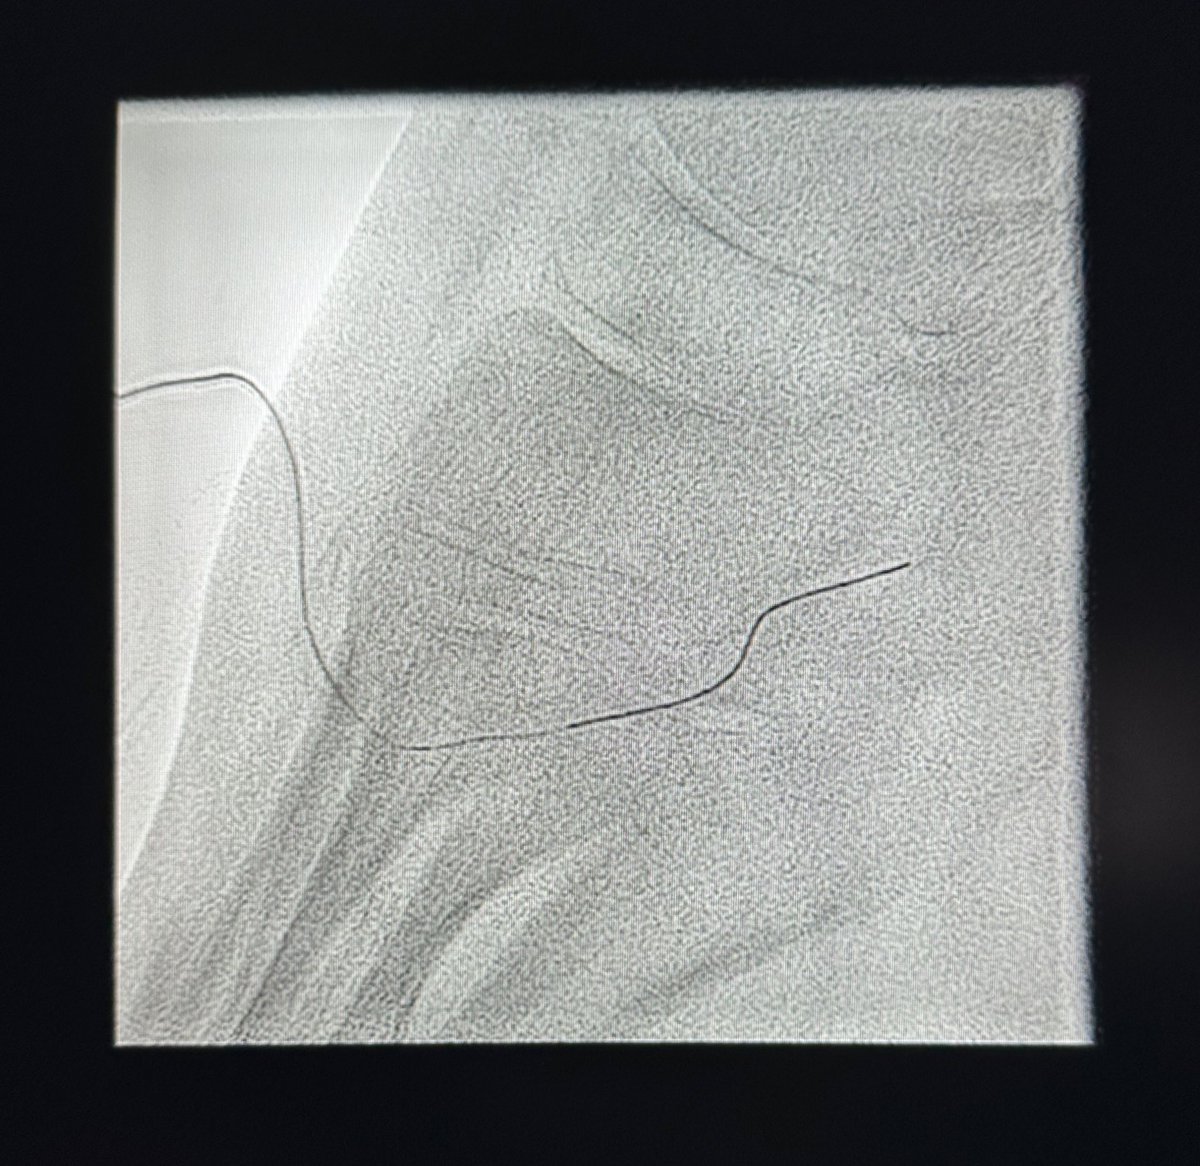

حالة من حالات نقص التروية الدموية الحاد مع وجود جرح غير ملتئم في القدم تم علاجها في وحدة #الأشعة_التداخلية بجامعة الملك سعود بالدخول من شرايين الفخذ والكاحل و إعادة فتح و توسيع الشرايين @ksumedicalcity @_KSU

د.سلطان رباح الحربي | Dr. Sultan R.Alharbi tweet mediaد.سلطان رباح الحربي | Dr. Sultan R.Alharbi tweet mediaد.سلطان رباح الحربي | Dr. Sultan R.Alharbi tweet mediaد.سلطان رباح الحربي | Dr. Sultan R.Alharbi tweet media

في وحدة #الأشعة_التداخلية بجامعة الملك سعود نقوم بتوفير أحدث التقنيات لعلاج القدم السكرية ونقص التروية. الدخول للشرايين يتم من الفخذ ، أو في بعض الحالات المتقدمة من الكاحل أو حتى من اخر القدم. بعض التقنيات لا توجد الا في أماكن قليلة جداً بالشرق الأوسط @ksumedicalcity @_KSU @ksu_medicine @FcmKsu